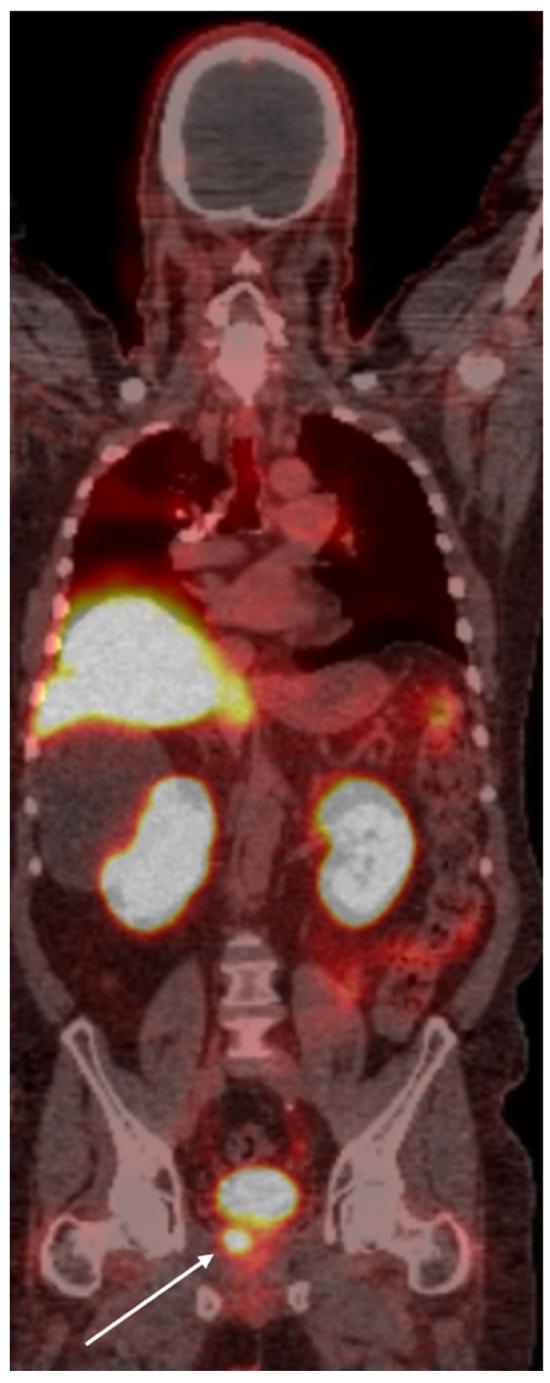

Prostate cancer, a leading cause of cancer-related mortality among men, is characterized by complex genetic and epigenetic alterations, dysregulation of oncogenic pathways, and a dynamic tumor microenvironment. Advances in molecular diagnostics and targeted therapies have significantly transformed the management of this disease. Prostate-specific membrane antigen (PSMA) has emerged as a critical biomarker, enhancing the precision of prostate cancer diagnosis and treatment. Theranostics, which integrates PSMA-targeted imaging with radioligand therapies, has shown remarkable efficacy in detecting and treating advanced prostate cancer. By leveraging the dual capabilities of PSMA-based diagnostics and therapeutic agents, theranostics offers a personalized approach that improves patient outcomes. This comprehensive review explores the latest developments in PSMA-targeted theranostics and their impact on the future of prostate cancer management, highlighting key clinical trials and emerging therapeutic strategies.

前列腺癌是男性癌症相关死亡的主要原因之一,其特征在于复杂的基因和表观遗传改变、致癌途径失调以及动态的肿瘤微环境。分子诊断和靶向治疗的进展显著改变了这种疾病的管理方式。前列腺特异性膜抗原(PSMA)已成为一种关键的生物标志物,提高了前列腺癌诊断和治疗的精准度。将PSMA靶向成像与放射性配体疗法相结合的诊疗一体化技术,在检测和治疗晚期前列腺癌方面已显示出显著疗效。通过利用基于PSMA的诊断和治疗药物的双重功能,诊疗一体化技术提供了一种个性化方法,可改善患者预后。这篇综述探讨了PSMA靶向诊疗一体化技术的最新进展及其对前列腺癌管理未来的影响,重点介绍了关键临床试验和新兴治疗策略。